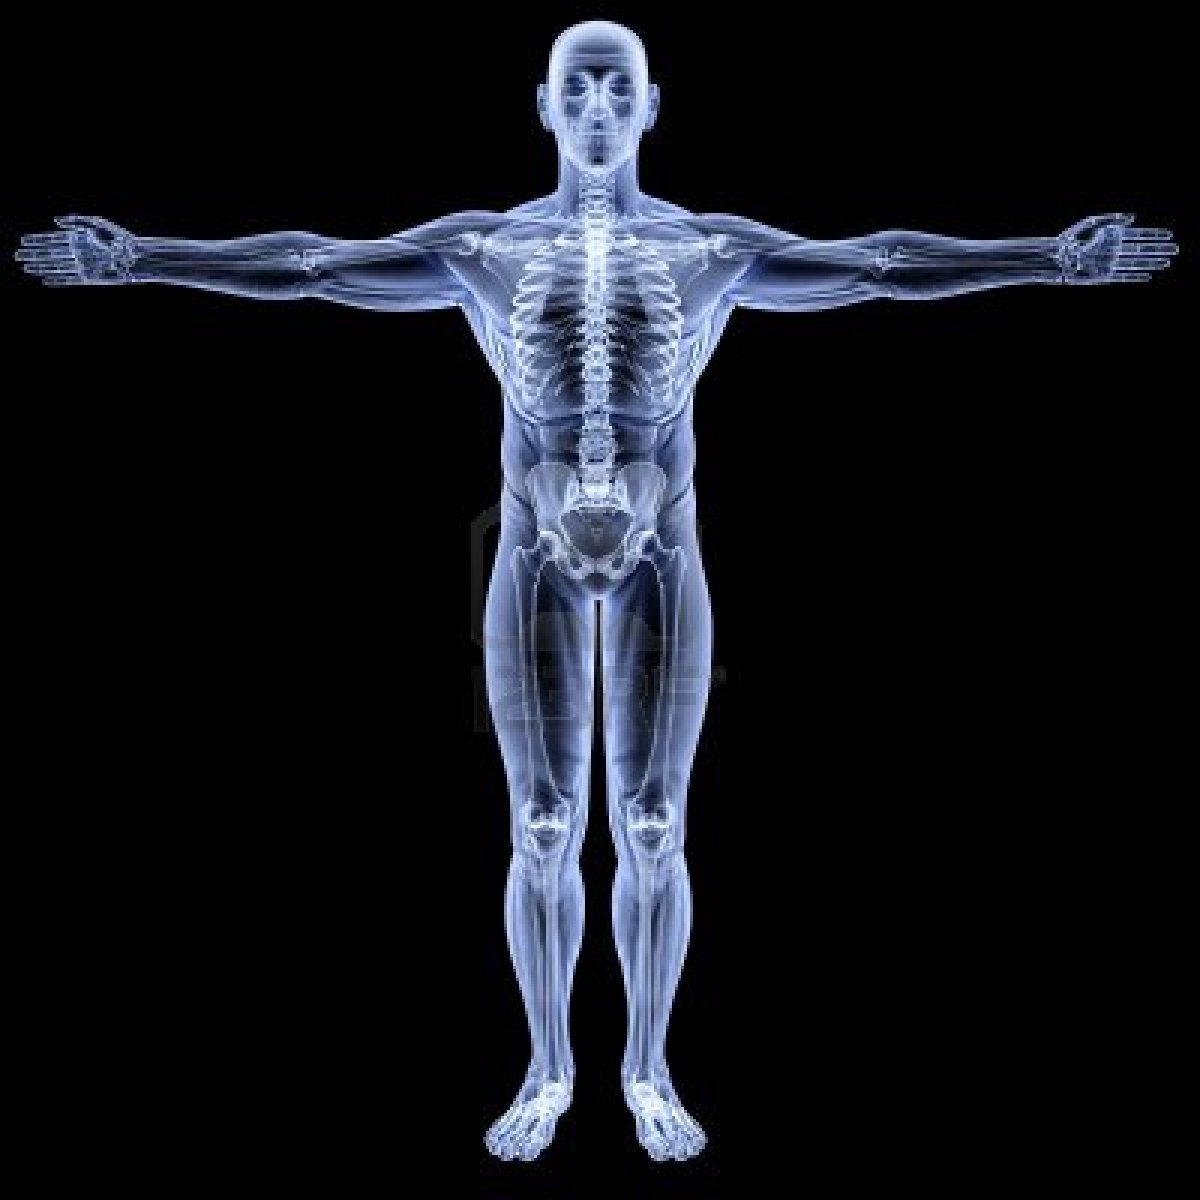

Xray, X-ray Of The Human Male Body. Royalty Free Stock Photos – Image …

Xray, X-ray Of The Human Male Body. Stock Illustration – Illustration …

Front view x-ray of a human body and skeleton Stock Photo – Alamy

X ray human body — Stock Photo © CLIPAREA #13280013